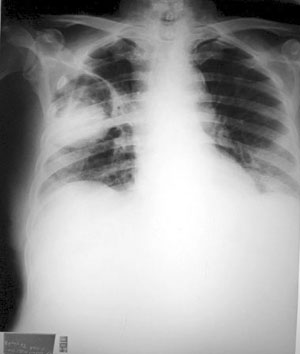

Aspergiloma. Con este término se refiere la formación de una masa fúngica en los pulmones de personas que tienen cavidades formadas previamente sin la participación de Aspergillus. Esto es, puede tratarse de pacientes que tiempo atrás sufrieron una tuberculosis cavitaria de la que incluso pueden haber sanado, sin embargo, si por accidente conidias de Aspergillus se depositan en la cavidad, entonces el hongo formará una masa fúngica que ocupara todo el espacio existente y posteriormente ocasionar inflamación y erosión de las paredes de la cavidad que se manifestaría clínicamente como hemoptisis. En las radiografías o tomografías se observará una masa redonda u ovoide en campos pulmonares que no presenta niveles hidro-aéreos (Figura 3).

Figura 3. Aspergiloma en el área central del campo pulmonar derecho. El paciente había presentado tuberculosis 5 años antes con resolución de la infección. Dr. LJ Méndez Tovar. Figura 4. Paciente femenina con aspergilosis pulmonar invasiva que presenta infiltrados difusos que afectan ambos campos pulmonares. Dr. LJ Méndez Tovar.

Los pacientes presentan sintomatología de una neumonía: disnea, tos, hipertermia y diaforesis. En las placas de rayos x, se observan infiltrados diseminados no característicos (Figura 4).